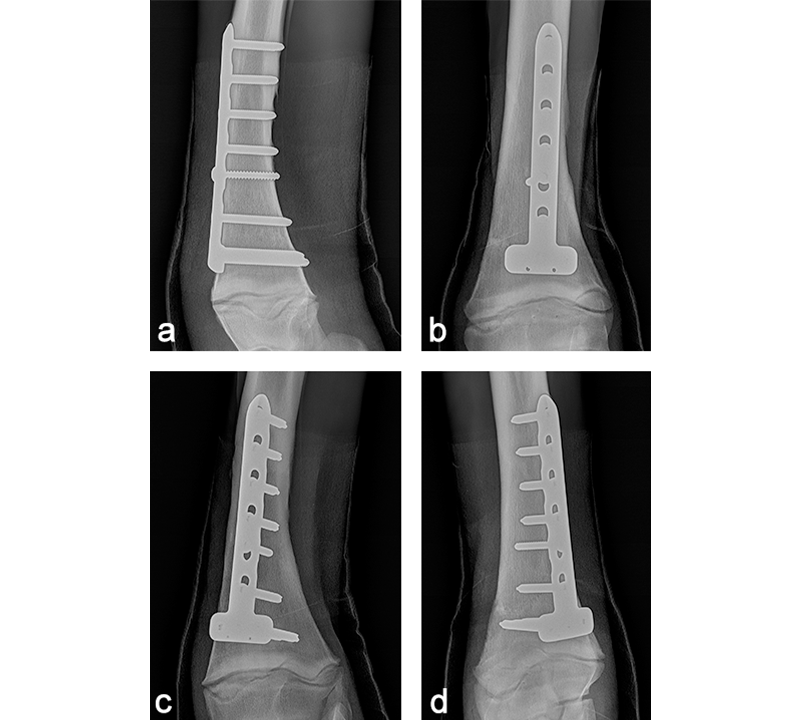

The foal was anesthetized and placed in dorsal recumbency. The left forelimb was placed in extension, clipped, prepared, and draped for aseptic surgery. A cranial approach to the distal aspect of the radius was made. The fracture was reduced, and a 6-hole LCP Equine T-Plate 4.5 was placed beneath the extensor carpi radialis (Fig 11). Two 5.0 mm locking screws were placed in the horizontal portion of the plate to engage the distal portion of the radius, just proximal of the distal radial physis. A 4.5 mm cortex screw was then placed into the second hole of the shaft of the plate, to provide interfragmentary compression and compress the plate to the proximal portion of the bone. The remaining holes were filled with 5.0 mm locking screws. The presurgical planning had included placing a second lateral LCP plate, however, the foals physiological status deteriorated. Further fracture fixation was therefore abandoned, and the surgery site was closed. A tube cast was placed from the level of the fetlock to the proximal radius. The foot and pastern were left free to minimize flexor tendon laxity. The foal was placed in sternal recumbency and required 2 hours of assisted ventilation before she started to breath spontaneously. Following surgery, she stood unassisted and was able to ambulate and suckle.

Postoperatively, the foal was noted to have a moderate carpus valgus deformity. Radiographic assessment, however, showed that the lateral deviation was not due to malalignment of the fracture. A gradual improvement in the degree of valgus deformity has been seen with growth as the foal has matured (Fig 13). Radiographic healing of the fracture has proceeded quickly with very little callus formation (Fig 14).